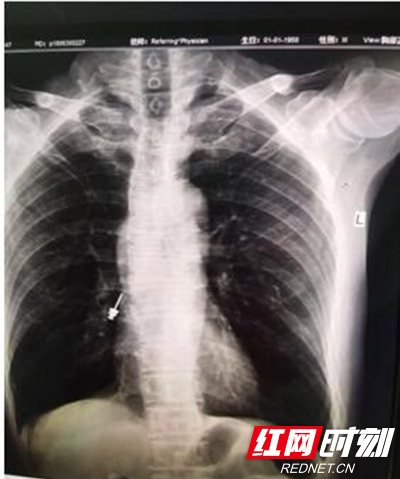

胸片示异物。

“马上做胸部CT,异物可能掉入气管。”伍友兴说到。果然不出所料,在CT室的电脑屏幕上,只见在位于患者右侧的支气管内,一颗注射器状的螺丝赫然在目。在支气管镜下,多位医生密切配合,通过鼻腔精准找到异物崁顿位置,小心地将极易滑落的异物由气管夹至鼻腔再推至口腔,长约2厘米的金属螺丝被成功取出,患者转危为安。